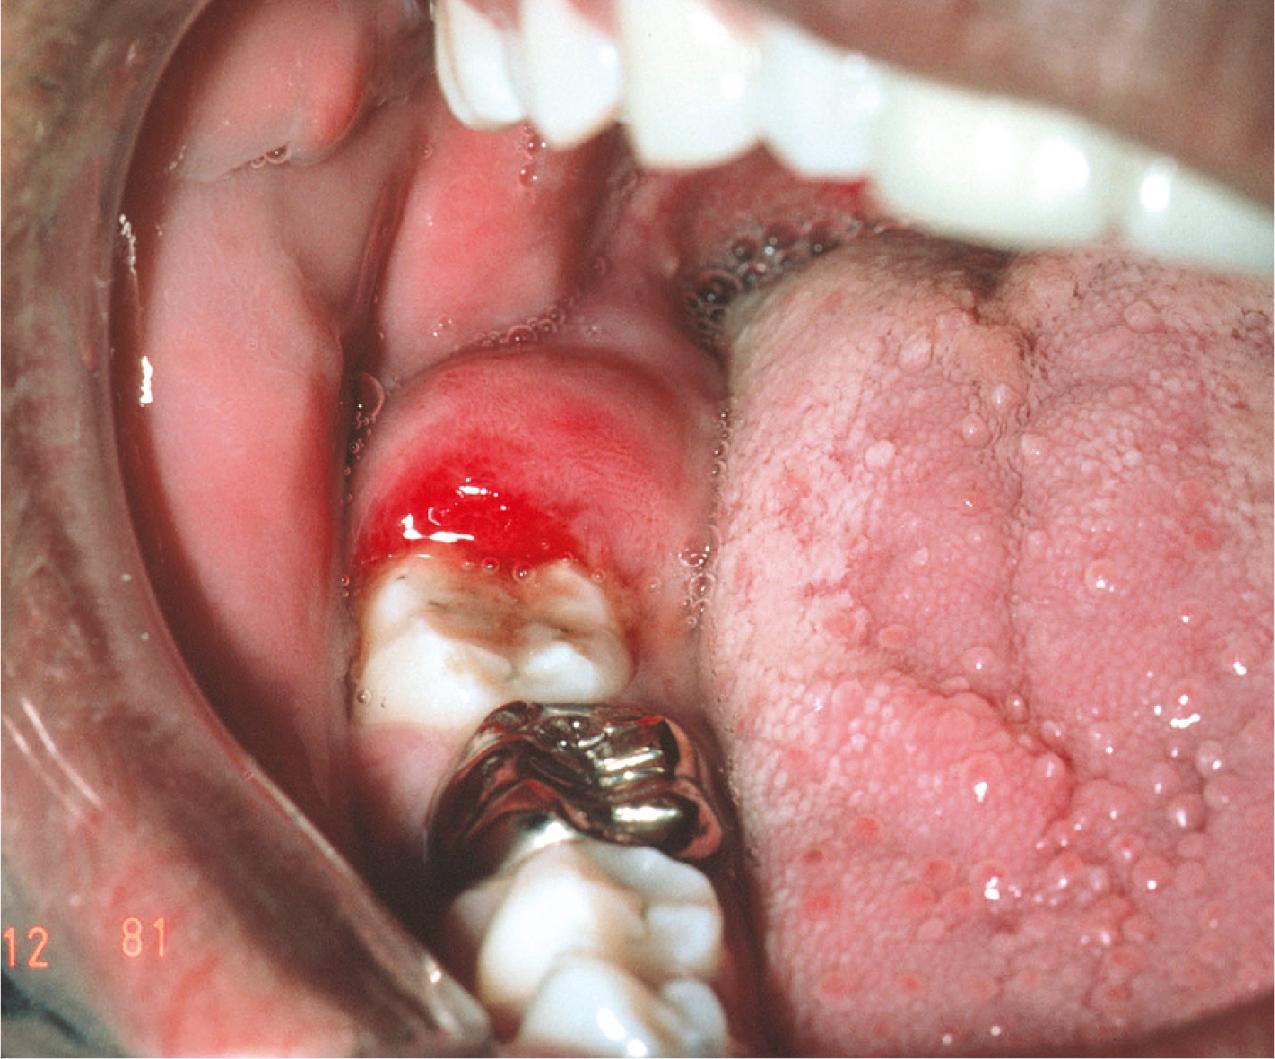

When a tooth is partially impacted with a large amount of soft tissue over the axial and occlusal surfaces, the patient frequently has one or more episodes of pericoronitis. Pericoronitis is an infection of the soft tissue around the crown of a partially impacted tooth and is usually caused by normal oral flora. In most patients, bacteria and host defenses maintain a delicate balance, but even normal host defenses cannot eliminate the bacteria ( Fig. 10.6 ).

Fig. 10.6, Pericoronitis in the area of impacted tooth #32 exhibiting classic signs of inflammation with erythema and swelling. If opposing tooth #1 is erupted, it commonly impinges on this area of swelling when teeth are brought into occlusion, causing even more pain and swelling.